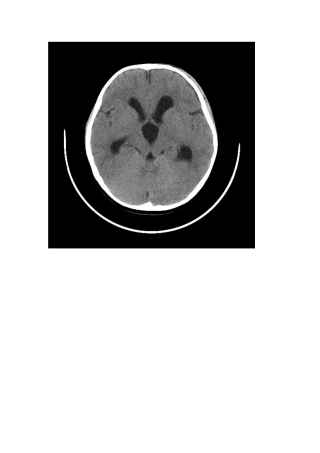

Galen大脑大静脉动脉瘤样畸形多见于新生儿及婴儿,婴幼儿及儿童约占90℅,成人约占10℅。正常大脑大静脉位于松果体后方,由双侧大脑内静脉...